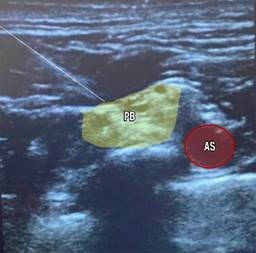

Para la anestesia regional se realizó primero el bloqueo del plexo braquial supraclavicular izquierdo ecoguiado, con el paciente en decúbito supino, en posición semifowler a 30o, la cabeza rotada hacia el lado derecho, transductor lineal de alta frecuencia (8-12 Mhz) en región supraclavicular paralelo a la clavícula, se identifica arteria subclavia, reborde de la primera costilla, pleura y divisiones del plexo braquial; en plano longitudinal se incide con aguja de neuroestimulación de 100 mm hasta el Corner Pocket; se infiltran 15 mL de ropivacaína al 0.5%, visualizando hidrodisección (Figura 1). El bloqueo del plexo braquial infraclavicular derecho ecoguiado fue el segundo bloqueo, con el paciente en posición semifowler, la cabeza rotada hacia el lado izquierdo; en plano parasagital justamente medial al proceso coracoides sobre la región pectoral colocamos el transductor lineal de alta frecuencia (8-12 Mhz); se localiza arteria axilar, vena axilar y cordones lateral, posterior y medial del plexo braquial, profundo a los músculos pectorales mayor y menor, se incide en plano longitudinal con aguja de neuroestimulación de 100 mm; se infiltran 15 mL de ropivacaína al 0.5%, visualizando hidrodisección (Figura 2).